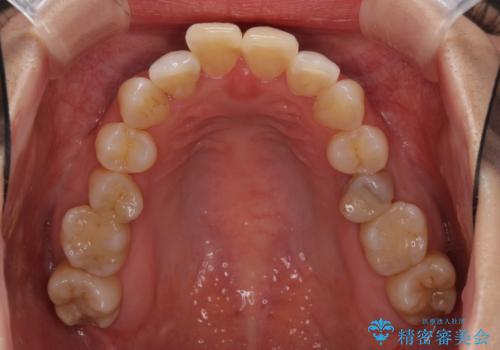

- 奥歯の咬み合わせを気にして来院された患者様です。

上顎骨の幅が下顎骨よりも小さいので、拡大装置により骨幅を広げて上下関係を改善し、その後インビザラインにて歯並びを整えることとしました。

上下の骨幅を改善したことで、スムーズに歯列矯正を行うことができました。

奥歯の咬み合わせを改善する必要があったため、治療は長期化しましたが、きっちりと仕上げることができました。